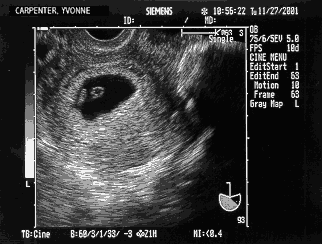

Matt: Without dragging it out we are still pregnant — for the moment at least. An ultrasound clearly shows a little membrane sac but it is just too early to be certain what is going on. Spots of blood or clots although not normal sometimes happens when the embryo implants into the uterus. On the other hand, we were also given the “it could be a ‘missed miss carriage’ and a sign that we are about to miscarry” speech. The doctor orders a series of blood tests to compare with the one Yvonne took yesterday where she scored a 31,000 and we are to return one week later. The number by itself does not say a whole lot but if the number goes up we are still pregnant and if it goes down we try again. We were also placed on “pelvic rest,” which in laymen’s terms means “no bed fun:-(” Other than that I went home somewhat relieved. Whatever was in there is still in there and it is just a matter of if it is going to stay in there. The week goes by VERY slowly. We got down to the business of having one of the first heated debates of our marriage; whether or not Yvonne is going to stop drinking Coke for 9 months. Ok, lets just say we have had a rather uneventful marriage as far as disagreements go. We survive this one just fine with no threats of divorce so the baby will have two parents when it is born;-)

Baby Carpenter at 6 weeks Matt: Our visit starts out on a bummer note when the doctor’s assistant says, “It looks like your numbers have gone down to 8,100.” My heart, or rather chest, was hit with a surge of adrenalin. Yvonne somehow says “Oh, OK.” Before I can say anything the assistant says, “Oh, I’m so sorry, I put the decimal place in the wrong spot, it is 81,000!” Ok, all is forgiven but that seems like the sort of thing you check before you open the door to tell two people if they are still pregnant or not. The doctor then comes in and all is forgotten because this women is just awesome. The more she talks the more I smile. As luck would have it they are testing a new ultrasound device so off we go. Right there in front of us we see our child’s first heartbeats! I still can’t stop smiling. Of course we ask tons of questions but the main point is we are back on track. Pictured is a scan of the ultrasound of our little embryo. By measuring the CRL (Crown Rump Length) the doctor says our baby is at 6 weeks — right on schedule. Below I enlarged a portion of it and scanned in some photos from a book, A Child is Born, to show what is going on at this time. I should say that there are two dates that get used when talking about a pregnancy. The common one which is the one we are using is the # of weeks since the start of the last “that time of the month” which for us was October 13th. Of course it is impossible to get pregnant at that time and so you end up with books showing pictures with captions like “at 6 weeks the 4 week old embryo” or “4 weeks since conception” etc. trying to account for the approximately 2 week difference. After a while the books then use the more common number as well but in those first weeks obviously 2 weeks can make a big difference. Point is I think I got the right pictures by editing and morphing several different photos that were taken before and after where we are. Oh, by the way, the doctor told us that on her first pregnancy she cut out all soft drinks as well:-) Oh, by the way part 2, it was a blood clot:-)